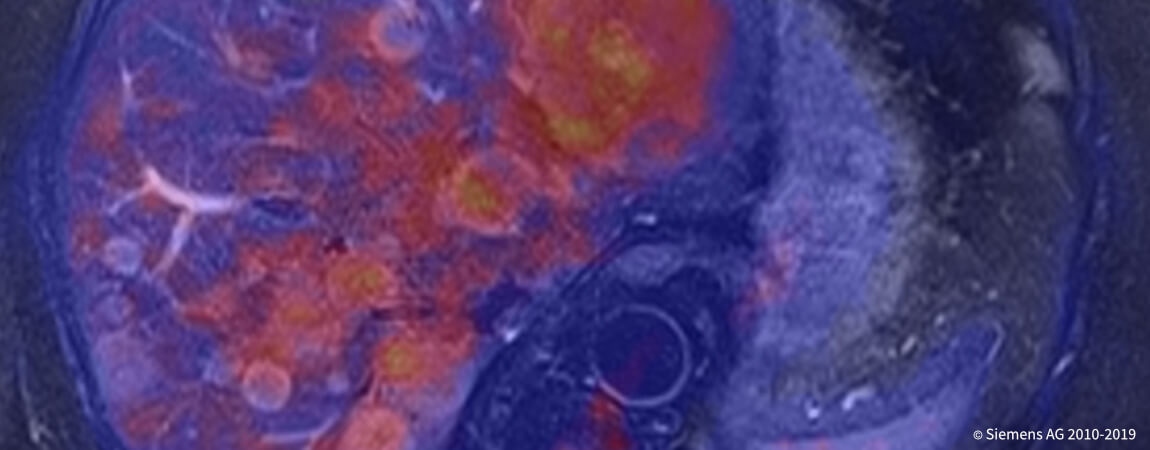

- _Все методы томографии